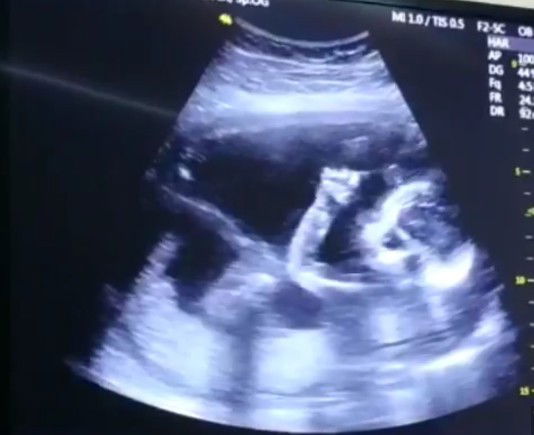

usg

apa disini ada yg sama kayak aku? pas usg 15week babbynya sehat lengkap semua alhamdulillah tapi posisinya tengkurep (ngadep bawah gtu) ini pict bukan pict usg aku kebetulan ga ada fotonya, kebanyakan kan posisinya ngadep atas kayak di pict gtu tapi bebny aku ngadepnya ke bawah, hehe ada yg sama??